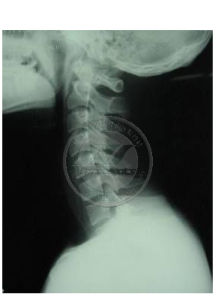

(1)動力學因素:Hiarayama等認為發病機制為反覆的屈頸動作或長期的維持屈頸姿勢導致已前置易位的硬脊膜從後方推壓頸脊髓,從而造成循環障礙,下頸髓前角運動細胞慢性缺血壞死。由此臨床試用頸圈治療本病有效,支持了一機制的可能。

平山病的病程自限,預後是良好的。目前有以下的治療方法:(1)頸托治療:早期診斷早期帶頸托治療,能縮短病程,緩解臨床表現。建議必須儘可能長時間帶頸托治療。(2)手術治療:研究表明做硬脊膜成形術加脊髓松解術,能改善近期和遠期效果。